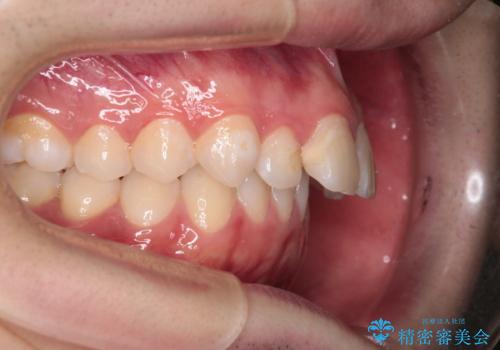

- 前歯が出ていることを主訴に来院されました。

臼歯関係が上顎前突傾向のため、上顎小臼歯を抜歯してインビザラインにて治療を行いました。

臼歯の咬合を作るために治療終盤ではゴムかけを行なっています。